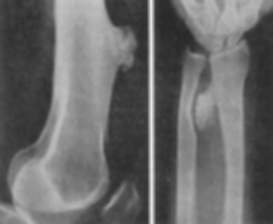

Tuberculoza osteoarticulara

Se manifesta prin zone de osteoliza - osteolizele pot sa fie marginale la nivelul corticalei, de dimensiuni mici (eroziuni) sau de dimensiuni mai mari ca în caria osoasa; zonele osteolitice situate în interiorul osului traduc cavernele tuberculoase. Osteolizele apar în majoritatea cazurilor pe fondul de demineralizare difuza ale extremitatilor epifizare; de obicei cavernele sunt situate epifizar; însa uneori pot avea sediul metafizar.